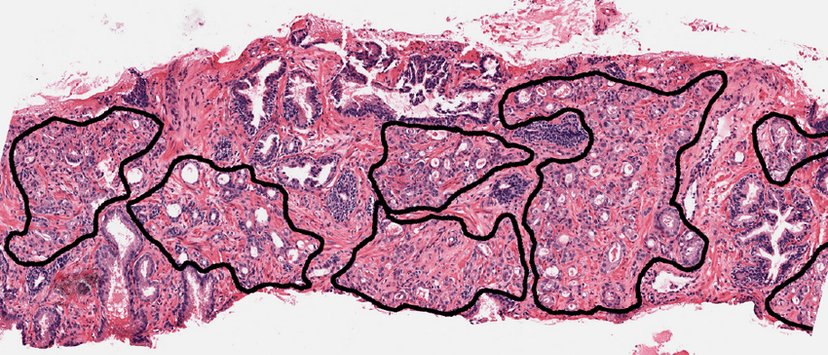

Oncology Pathology Annotation

Comprehensive oncology pathology annotation including WSI slides and tissue/cell level analysis for cancer diagnosis, staging, and research.

Key Features:

- •Whole Slide Imaging (WSI) annotation

- •Tumor region segmentation

- •Cell morphology classification

- •Mitosis counting and scoring

- +10 more capabilities